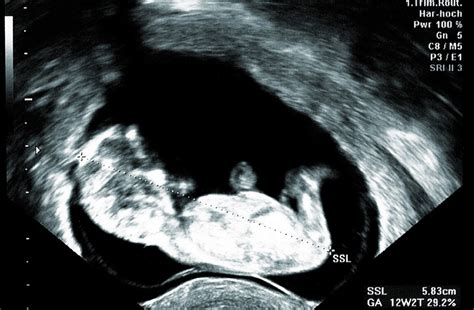

V 16. týždni tehotenstva už bábätko pripomína svojou veľkosťou avokádo. Jeho dĺžka od temena po kostrč (CRL) sa pohybuje okolo 11,5 cm a váži približne 100 gramov. Celková dĺžka tela od hlavičky po päty môže dosahovať 13 až 18 cm. Táto fáza je charakteristická rýchlym rastom a zdokonaľovaním telesných funkcií.